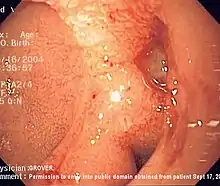

| Endoscopic image of a posterior wall duodenal ulcer with a clean base, which is a common cause of upper gastrointestinal hemorrhage and could potentially lead to perforation. | |